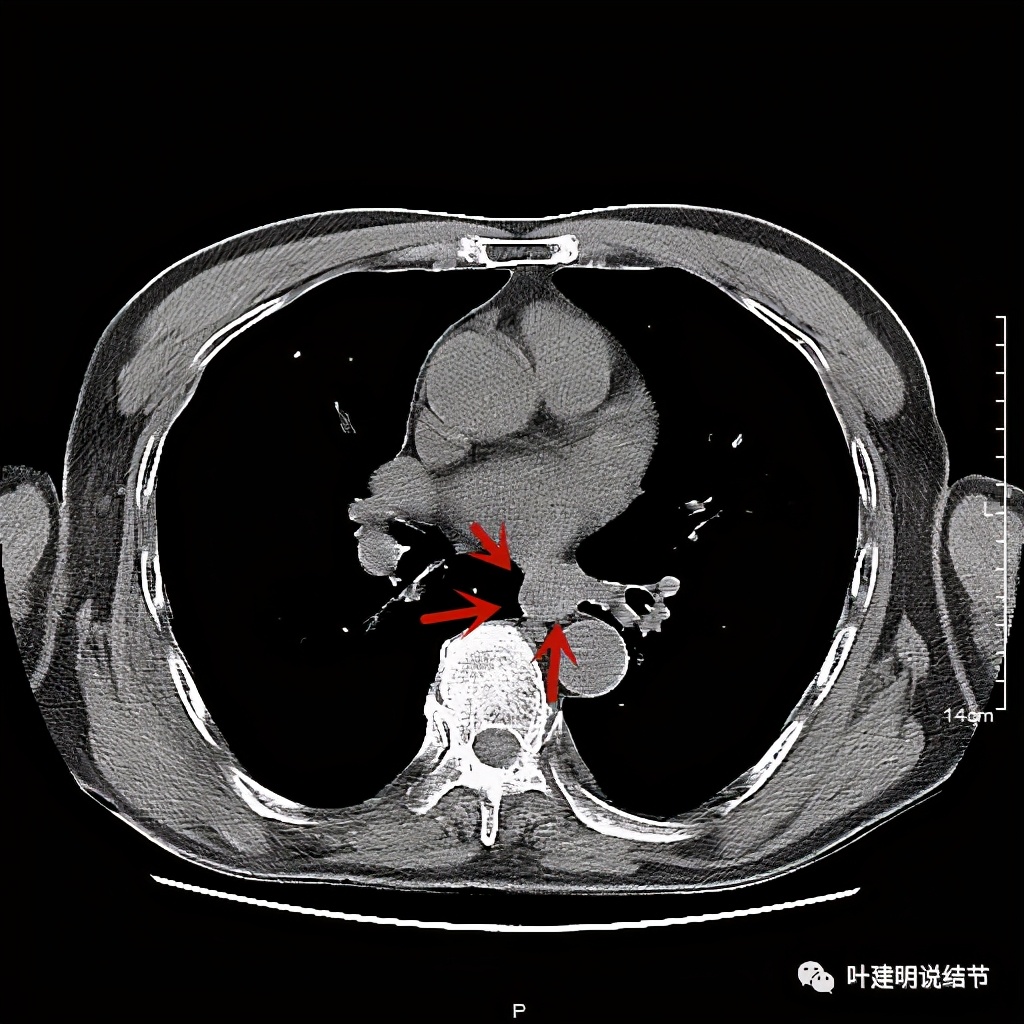

活检后食管是鳞癌,结肠是腺癌。下面是其术前CT的图像:

红色示肿瘤

红色示肿瘤,桔色示下肺静脉,与主动脉间间隙清楚